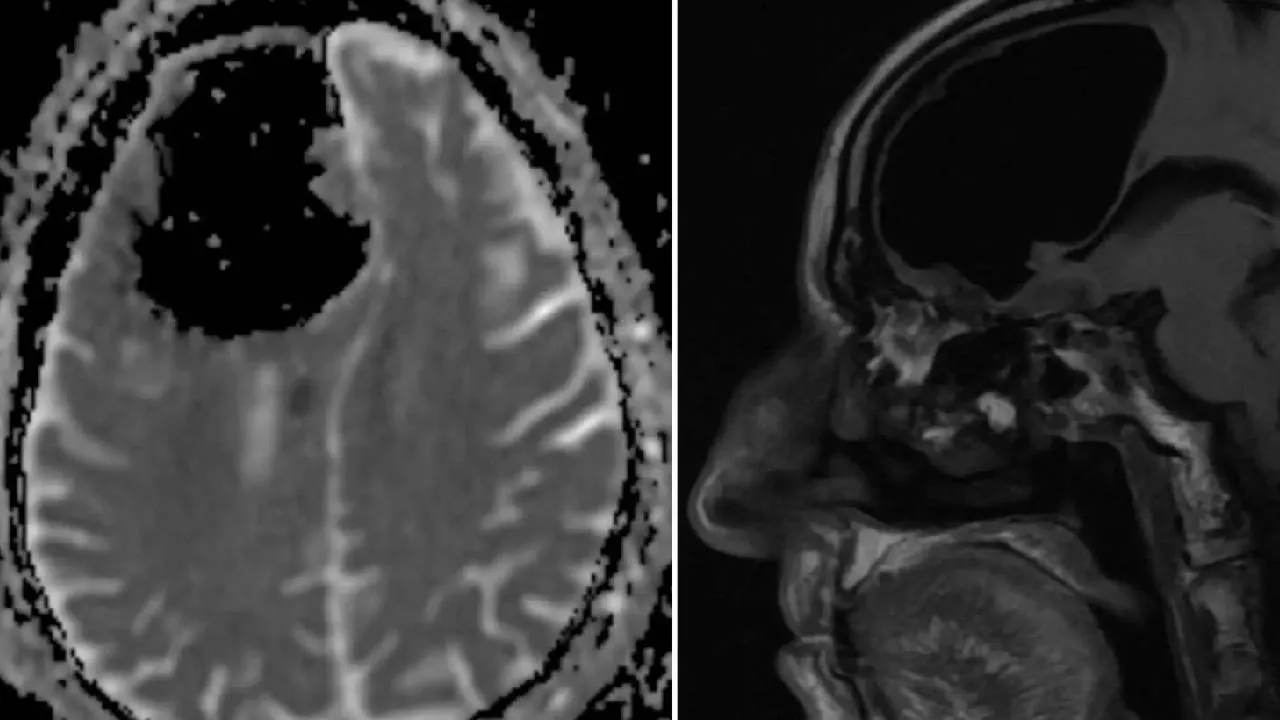

ಹೈಡ್ರೋಸೆಫಾಲಸ್ (ಜಲಮಸ್ತಿಷ್ಕ ರೋಗ) ಎಂಬ ಅಪರೂಪದ ಕಾಯಿಲೆಯಿಂದ ಬಳಲುತ್ತಿದ್ದ ಫ್ರೆಂಚ್ ವ್ಯಕ್ತಿಯೊಬ್ಬನಿಗೆ ಸಿಟಿ ಸ್ಕ್ಯಾನಿಂಗ್‌ ಮಾಡಿದಾಗ ಅದರಲ್ಲಿ ಅವನ ಮೆದುಳು ಶೇಕಡ 90 ರಷ್ಟು ಖಾಲಿಯಾಗಿರುವುದು ಕಂಡುಬಂದಿದೆ. ಆದರೆ ಸಿಟಿ ಸ್ಕ್ಯಾನ್‍ ರಿಪೋರ್ಟ್‌ನಲ್ಲಿ ಬೇರೆಯೇ ಇದೆ ಎಂದು ನರರೋಗ ತಜ್ಞರು ತಿಳಿಸಿದ್ದಾರೆ.ಈ ಸುದ್ದಿ ಈಗ ವೈರಲ್‌(Viral News) ಆಗಿದೆ.

ಮನುಷ್ಯನ ತಲೆಯಲ್ಲಿ ಮೆದುಳು ಇಲ್ಲದಿದ್ದರೆ ಮನುಷ್ಯ ಜೀವಂತ ಶವವಾಗುತ್ತಾನೆ ಎಂಬುದು ಎಲ್ಲರಿಗೂ ತಿಳಿದ ವಿಚಾರ. ಹೀಗಿರುವಾಗ ಹೈಡ್ರೋಸೆಫಾಲಸ್ (ಜಲಮಸ್ತಿಷ್ಕ ರೋಗ) ಎಂಬ ಅಪರೂಪದ ಕಾಯಿಲೆಯಿಂದ ಬಳಲುತ್ತಿದ್ದ ಫ್ರೆಂಚ್ ವ್ಯಕ್ತಿಯೊಬ್ಬನಿಗೆ ಸ್ಕ್ಯಾನಿಂಗ್‌ ಮಾಡಿದಾಗ ಅದರಲ್ಲಿ ಅವನ ಮೆದುಳು ಶೇಕಡ 90 ರಷ್ಟು ಖಾಲಿಯಾಗಿರುವುದನ್ನು ನೋಡಿ ವೈದ್ಯರು ಶಾಕ್‌ ಆಗಿದ್ದಾರೆ. ಹೀಗಿದ್ದರು ಆತ ಯಾವುದೇ ಮಾನಸಿಕ ಸಮಸ್ಯೆಗಳಿಲ್ಲದೆ ಕೆಲಸ ಮಾಡುತ್ತಿದ್ದಾನೆ ಮತ್ತು ಕುಟುಂಬವನ್ನು ನಿರ್ವಹಿಸುತ್ತಿದ್ದಾನೆ. ಈ ಸುದ್ದಿ ಈಗ ಸೋಶಿಯಲ್‌ ಮೀಡಿಯಾದಲ್ಲಿ ವೈರಲ್‌ ಆಗಿದೆ.

ಏನಿದು ಮೆದುಳು ಖಾಲಿಯಾಗುವುದು ಎಂದು ನಿಮಗೂ ಕೂಡ ಆಶ್ಚರ್ಯವಾಗ್ತಿದೆಯಾ...? ನರರೋಗ ತಜ್ಞರ ಅವರ ಪ್ರಕಾರ, ಇಲ್ಲಿ ಮೆದುಳು ಖಾಲಿಯಾಗಿಲ್ಲ, ಬದಲಾಗಿ ಸಿಟಿ ಸ್ಕ್ಯಾನ್‍ ಮೆದುಳಿನಲ್ಲಿ ತುಂಬಿಕೊಂಡ ನೀರನ್ನು ತೋರಿಸುತ್ತದೆ. ಖಾಲಿ ಸ್ಥಳವಲ್ಲ. ಈ ನೀರನ್ನು ಸೆರೆಬ್ರೊಸ್ಪೈನಲ್ ದ್ರವ ಎಂದು ಕರೆಯಲಾಗುತ್ತದೆ. ಇದು ಮೆದುಳು ಮತ್ತು ಬೆನ್ನುಹುರಿಯನ್ನು ಸುತ್ತುವರೆದಿರುವ ಸ್ಪಷ್ಟವಾದ ಬಣ್ಣ ರಹಿತ ದ್ರವ ಆಗಿದೆ. ಸೆರೆಬ್ರೊಸ್ಪೈನಲ್ ದ್ರವ ಮೆದುಳಿಗೆ ಪೋಷಕಾಂಶ ಕಳುಹಿಸುತ್ತದೆ. ಹಾಗೂ ಕಲ್ಮಶಗಳನ್ನು ತೆಗೆದು ಹಾಕುತ್ತದೆ.

ಈ ದ್ರವವು ಮೆದುಳಿನ ಅಂಗಗಳ ಸುತ್ತಲೂ ಹರಿಯುತ್ತದೆ ಮತ್ತು ಪ್ರತಿದಿನ ಉತ್ಪತ್ತಿಯಾಗುತ್ತದೆ. ಹೆಚ್ಚುವರಿ ದ್ರವವು ಸಂಗ್ರಹವಾದಾಗ, ಅದು ಜಲಮಸ್ತಿಷ್ಕ ರೋಗಕ್ಕೆ ಕಾರಣವಾಗುತ್ತದೆ. ಇದು ಸಿಟಿ ಸ್ಕ್ಯಾನ್‌ಗಳಲ್ಲಿ ಕಪ್ಪು ಪ್ರದೇಶವಾಗಿ ಕಾಣಿಸಿಕೊಳ್ಳುತ್ತದೆ. ಆದರೆ ಈ ಭಾಗವು ಖಾಲಿಯಾಗಿಲ್ಲ ಅದು ದ್ರವದಿಂದ ತುಂಬಿರುತ್ತದೆ.